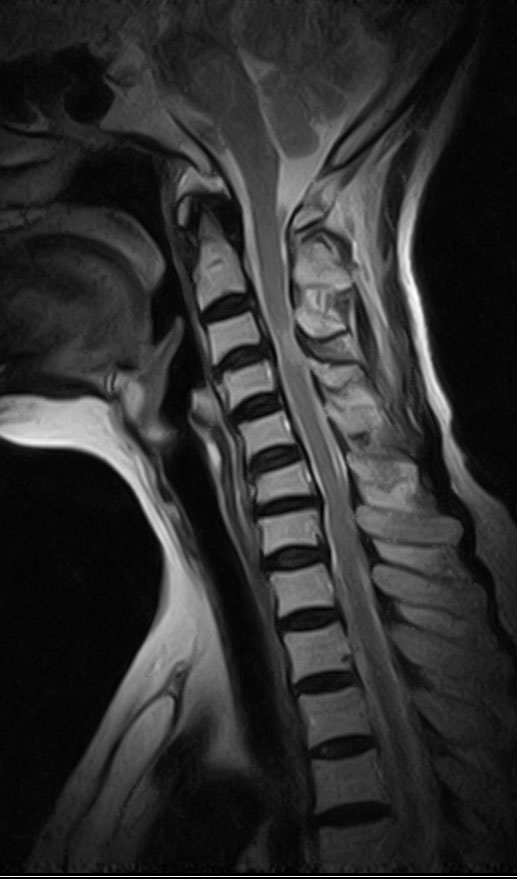

20090603190823迵#ö@$ mri Դϴ ϼ. [ֹȣ : 20090603190823cccp14] 迵* ֹ ֹϽ : 2009-06-03 19:08:23 㼱 ֹID cccp14 (cccp14@naver.com) ֹ »: 迵* Ա: * º: 迵* ȭ: 031-812-**** / 010-****-4404 ּ: ȣ : 412-@@@ ּ : 籸 굿 *** 115-802 : 2009-06-05 ũ (Ư , ) հ ϰ հ ĥĥ A/S մϴ 6094703159967(Ȯ6/5) ۿ Ա ݼ Ű 146 41 76 ˰Ե ͳ õ ͳ ˻ڷ õ ش 1C.ڵ, 1C.ٽŰ 1C.ٿ, 1C. 1C.ٺҸ, 1C.پǸ, 1C.ٰ 1C.ٽŰ, 1C.ٸǷ 1C., 1C.ں 1C.ټ Ǹ 1C.ٱ () 1C.߷ () 1C.Ƿ () 1C.̸, 2C.ڽ÷ 4C. 4C.û° 4C.5C.ھ, հ 6C. κ 6C.ھ Ḳ ()ũ( ߰Ż) ڸ(߹) Ը Ͽ ũ(߰Ż), ũ(߰Ż)ġ, հ , , հ , ġ, , Ḳ , , Ḳ ġ Ҹ ġ Ǹ, Ϸ 2ȸ ̻ ῡ ġ Ǵ ġ ħ Ʈ 氨 Ƿ ġ |